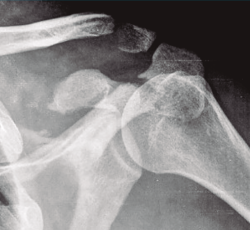

La cintura escapular es el segmento proximal del miembro superior. Fija la articulación glenohumeral al tronco, de manera que constituye la comunicación entre el miembro superior y el tronco. La cintura escapulohumeral se encuentra formada por: clavícula, escápula y húmero proximal (Figura 1)(1).

Figura 1. Anatomía de la cintura escapulohumeral.